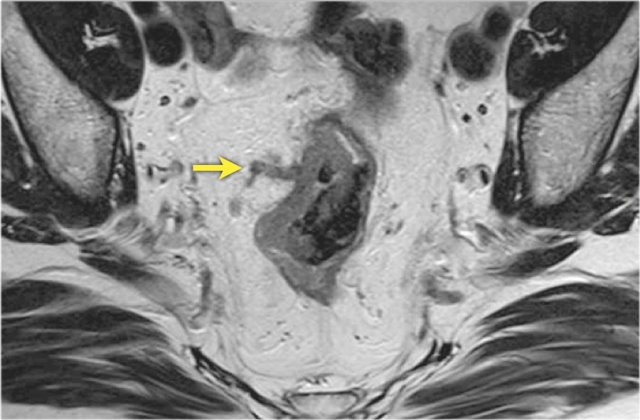

On MRI signet-ring cell carcinomas can be difficult to

discern, though they typically show long-segment diffuse bowel wall thickening

and a submucosal growth pattern that results in a ‘target’ appearance on axial

images.

The images show a signet-ring cell carcinoma with diffuse thickening of the rectal wall and the target appearance on the axial image. Also note the diffuse infiltration of the mesorectal fat, which is another common finding of signet ring tumors.